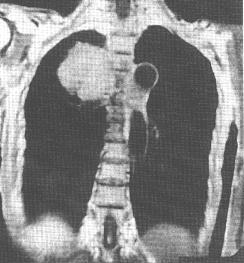

2)x線檢查,下肢的淋巴管造影,對確定腹膜後淋巴結受侵有一定價值。對其他可疑的部位作x線攝片和造影檢查亦很有診斷價值。

3)CT檢查,對縱隔、肺、肝、脾、腹部、腹膜後、盆腔等部位的占位病變,有很高的診斷價值。